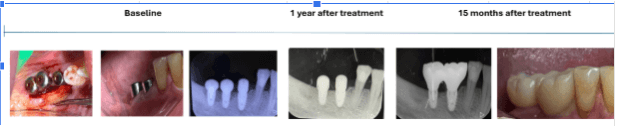

Case Summary: A 35-year-old female presented with a red, edematous bulge (2.5 mm diameter) two months after implant placement in site #45, previously extracted due to vertical root fracture. A periapical X-ray revealed early signs of bone loss at the coronal level, indicating inflammatory environment onset.

Treatment Approach: A Magdent MED healing abutment was placed for 60 days to deliver localized PEMF therapy and promote tissue regeneration around the implant.

Clinical Outcome:

• Inflammation and edema fully resolved

• Bone density and level significantly improved (confirmed via X-ray)

• Implant clinically stable and asymptomatic